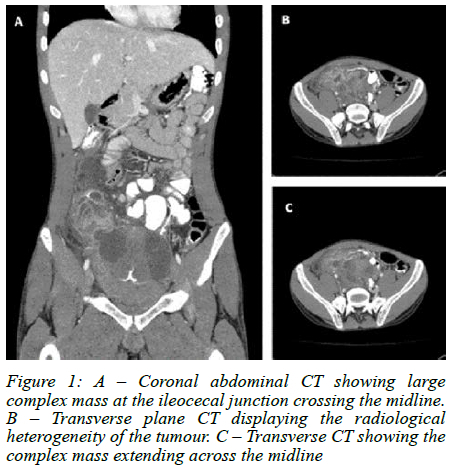

Urgent computer tomography (CT) imaging suggested a complex pelvic mass, likely ileocaecal in origin (Figure 1). He underwent emergency laparoscopy converted to laparotomy which revealed a complex perforated terminal ileum mass 10 cm from the ileocaecal junction (Figure 2). An ileocecectomy with primary anastomosis was performed. Histology confirmed metastatic embryonal rhabdomyosarcoma with 1 out of 14 mesenteric lymph nodes involved. Our patient had an uneventful postoperative course and was discharged in a stable condition. He is currently undergoing palliative chemo-radiotherapy for spinal, liver and lung metastases.